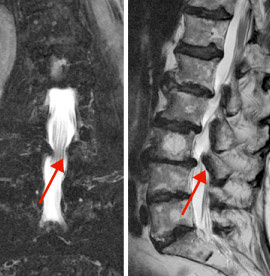

hirslanden-wirbelsaeuleneingriffe-beim-alternden-menschen-2

Abb. 2

Degenerative Skoliose mit schiefer Körperhaltung

Deformitäten der Wirbelsäule

Verkrümmungen der Wirbelsäule treten frontal (Skoliose) oder seitlich (Kyphose) auf, meist in instabiler Form, d.h. beim Stehen, Gehen und Sitzen nimmt die Verkrümmung zu und im Liegen wird sie korrigiert. Dies kann zu deutlichen lageabhängigen Rücken- und Beinschmerzen mit oder ohne neurologische Ausfälle führen. Bleibt die konservative Therapie erfolglos, steht ein eingreifendes und schwerwiegendes chirurgisches Verfahren mit mehretagerer Fixation und Aufrichtung der deformierten Wirbelsäule mit oder ohne Dekompression des Wirbelkanals zur Diskussion. Hier gilt es, insbesondere bei älteren Menschen, den Nutzen des Eingriffs und die damit verbundenen Risiken sorgfältig abzuwägen (Abb. 2).